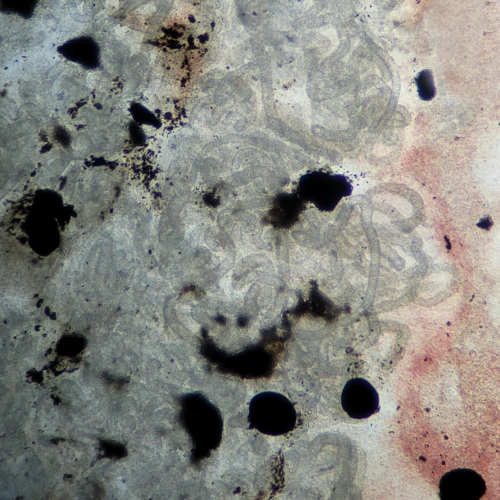

Microcirculatory disturbances lead to venous congestion, increased pressure, and vascular damage. These changes reflect the development of ischemia in nervous tissue.

The trunk kidney lies along the позвоночник beneath the swim bladder and contains renal tubules — the main functional structures. A large volume of blood passes through it, so microcirculatory disturbances quickly lead to pronounced changes.

Typical findings include:

- hyperemia

- tubular destruction

- tissue necrosis